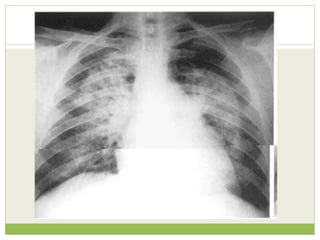

Clinical information provided ๏‚—Recent increase in shortness of breath ๏‚— No fever or productive cough ๏‚— Left shoulder and arm pain ๏‚— Heavy smoker ๏‚— Weight loss

Findings Left apical shadowing Raisedleft hemidiaphragm Increased extra-thoracic soft tissue density (*) with displacement of the scapula on the left (arrowheads) - compare with right

๏‚— Interpretation inview of clinical details ๏‚— Cancer - Smoker with weight loss and left apical consolidation/mass and no clinical features of infection ๏‚— Phrenic nerve palsy - Increased shortness of breath and raised left hemidiaphragm ๏‚— Brachial plexopathy - Arm pain and axillary soft tissue swelling